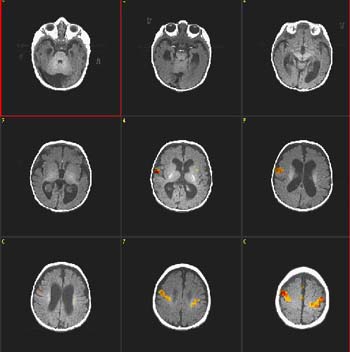

fMRI Studies (Functional Magnetic Resonance Imaging)

What is fMRI?

Functional magnetic resonance imaging (fMRI) is a development of MRI techniques that allows visualization of brain functions related to specific tasks. The study does not require any substance to be administered since it is based on the indigenous brain vascular response, requiring only cooperation for periods ranging from 15 to 60 minutes.

To date, several tasks have been utilized for mapping the brain cortex. Simple tasks include stimuli based on presentation of light, colors, tones, chords, music, syllables, movement of fingers and basic sensory perceptions. More complex and refined experiments have been implemented to map subtle cognitive functions. Currently, there is a vast armamentarium for mapping memory, attention, inhibition, face recognition, sensory discrimination, fear, etc.

However, most fMRI work has been directed in mapping language. Language mapping has been performed in children and adults. Reading, listening to meaningful text, generating words, making semantic decisions, are the most frequent paradigms described in the abundant current literature on fMRI. The technique has received ample acceptance among neuroscientists interested in epilepsy for the potential it has to become a tool to replace the Wada test.

Functional MRI is based on small signal changes that result from the following cascade of events. A task elicits activation in one or several brain areas. These areas increase their metabolic demands, suffer vasodilatation, and alter their levels of deoxyhemoglobin and oxyhemoglobin. Since deoxyhemoglobin is a paramagnetic molecule, it influences the phase of local proton-spins, altering the source signal that is converted into images. Therefore, the image is a representation of local changes of levels of deoxyhemoglobin, related to the brain region performing a task.

Although fMRI is almost risk-free, it cannot be performed in patients with claustrophobia, metal implants, wires and pace-makers. Patients with vagal nerve stimulators, or dental braces, may be included. However, some degradation of the images is expected.

Research and studies conducted by:

Dr. Nolan Altman and Dr. Byron Bernal of the Radiology Department

Clinical Cases Language Mapping Auditory Mapping 3D fMRI